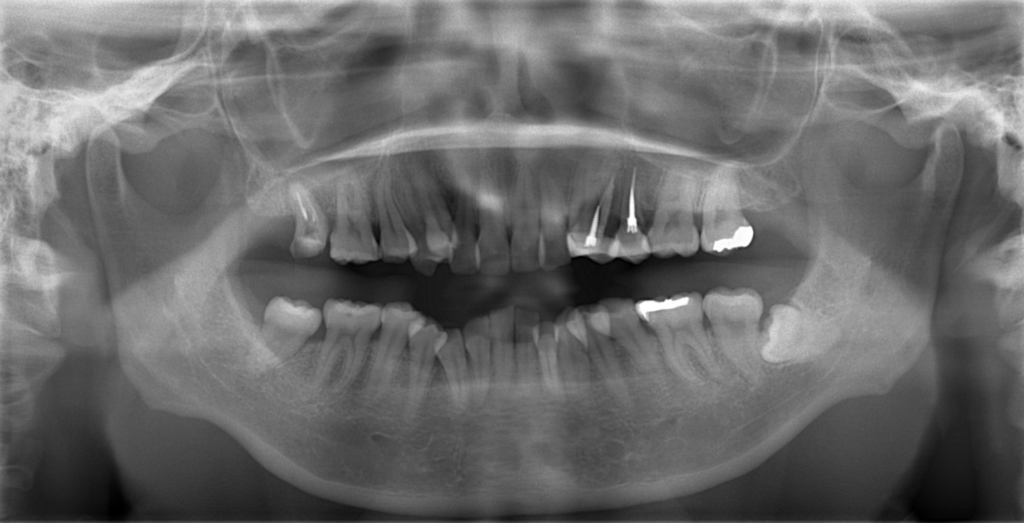

レントゲン写真で確認すると、

この患者さんの場合、

#1.顎と歯の不調和による叢生(重度)

#2.上顎前突(出っ歯)傾向

と診断しました。